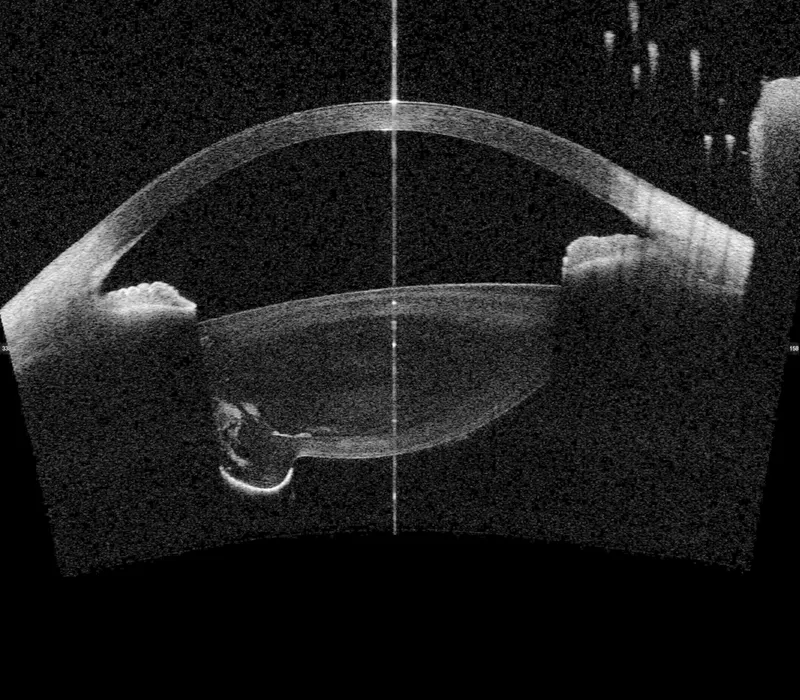

💡 Master This: The "dark room prone provocative test" exploits pupillary block physiology-having patient lie prone in darkness for 60 minutes causes pupil dilation and anterior lens shift. IOP rise >8 mmHg or angle closure on gonioscopy indicates high acute attack risk. However, sensitivity is only 50-60%, limiting clinical use; anterior segment OCT showing angle opening distance <500 μm is more reliable.